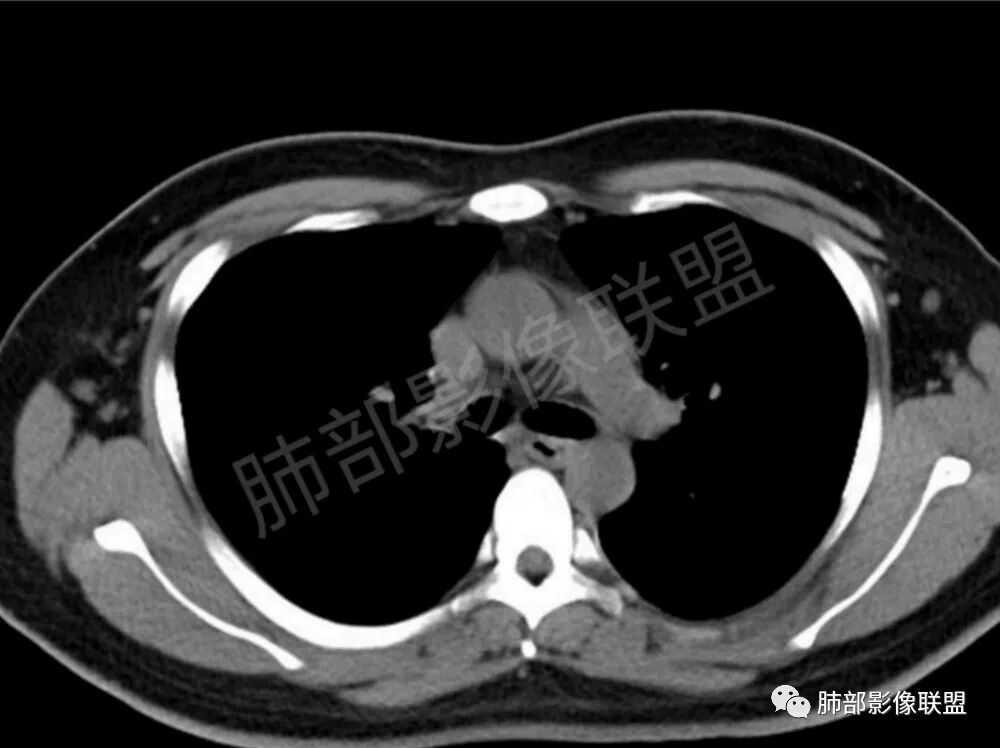

男性,22岁,HIV病史,症状半年,双肺多发大小不等结节影,边缘光滑,密度均匀,以胸膜下分布为主,部分与胸膜相连,胸膜下脂肪间隙可见,病灶近段支气管走行病灶内,远端似有堵塞,无增强图像,考虑隐球菌,鉴别:淋巴瘤,GPA

双肺多发结节影,膨隆,边缘光滑,圆顿,沿支气管血管束分布为主,部分贴胸膜,部分见空洞,空气支气管征

两肺多发结节性,大部分位于胸膜下,部分结节周围可见晕征。局部结节内可见扩张的支气管,纵隔淋巴结大,脾大,22岁男,HIV阳性,常规先考虑隐球菌。鉴别淋巴瘤,结核,马儿。

男,22,半年前咳嗽伴少痰,查HIV阳性,痰查TB阳性,既往有肺部斑片影伴空洞、纵隔淋巴结肿大、脾大。SCC、CA50、CA199、FER增高,此次胸部CT:两肺多发结节影,部分沿血管束分布,部分贴胸膜下,大小不一,密度不一,部分较散、边缘模糊,部分较实、圆钝、周围模糊晕,部分结节有支气管进入穿行自然,部分结节有血管分支自如通过。考虑HI∨相关淋巴增殖类病变,淋巴瘤?LYG?鉴别PC、TB。

青年男性,半年前咳嗽,HIV阳性,结核DNA阳性,肿标糖类抗原和铁蛋白增高。外院影像有纵隔淋巴结增大伴脾大,肺部病灶空洞。现在影像:肺内多发沿支气管分布(有支气管充气征,长轴沿支气管分布)及胸膜下分布(平行于胸膜)的大小不等结节,个别伴有空洞,双侧腋窝淋巴结肿大。纵隔图片不够,是否还有淋巴结肿大未知,脾脏未显示。

1.双肺多发大小不一结节,外围为主,边界尚清,部分周围似有GGO

2.类圆形,部分与胸膜相连,糊墙

3.支气管通畅或近端堵塞

影像学缺乏特征性,以支气管血管周围、胸膜下及双肺下叶周边多发结节影最多见,结节易坏死形成空洞,伴有游走性和多变性的特征,结节周围可有磨玻璃样晕征,有时也可见单发结节影、薄壁的囊状阴影或弥漫性浸润影。肺门、纵隔淋巴结肿大少见, 可见胸腔积液和气胸。

肿块型∶表现为两肺多发大小不等的不规则肿块,肿块边缘不光整、欠锐利,有大的分叶,毛刺少见,增强扫描呈明显强化,可合并坏死、空洞;

结节型∶表现为两肺多发大小不等的结节,以两肺中下野多见,结节边缘欠锐利;